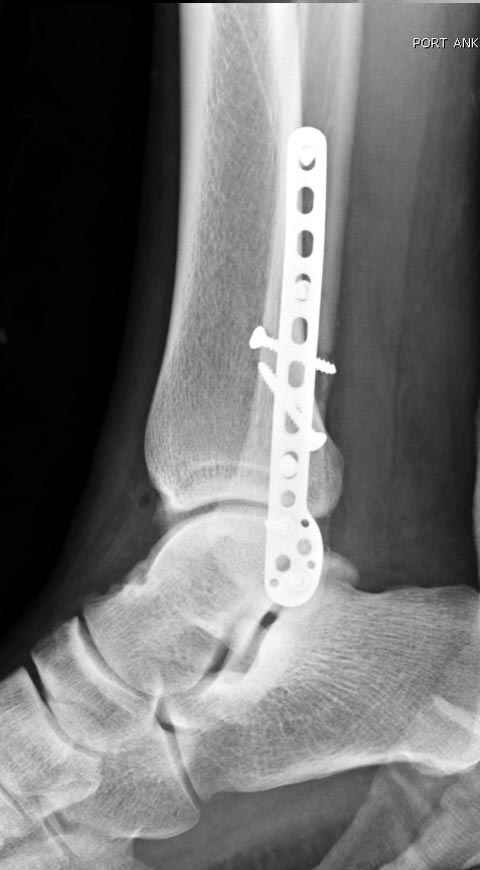

Уважаемые коллеги! Как и обещал, представляю плоды своей работы. Хвалиться особо нечем. Пошли задним

доступом сначала к м/берцовой кости, благодаря смещению линию перелома удалось сразу дифференцировать и по ней узким долотом (без молотка) мобилизовали отломки. Затем выделили задний край, там было проще пройти по линии перелома. Далее пластина по задней поверхности в дистальный отломок, винт проксимальнее пластины и дистрактором с трудом растянули отломки, ощущение было идеальной репозиции м/берцовой кости( доступен осмотр по задней и наружной поверхности), далее винты стандартно. Кстати, положение больной на боку: очень неудобно, но по-другому потом не повернуть на спину, чтобы сделать снимки в стандартных проекциях (ЭОПа нет). Затем дистрактор (два полукольца, спицы), репозиция заднего края, спонгиозный винт с шайбой, слишком проксимально, поэтому + еще один. Доступ к дельтовидной связке: рубец в передней порции, частично иссечен, шов. В общем, длительность операции 3,5 часа, а сказать, что все задуманное получилось, не могу.

А.Минервин.

Отличная, грамотная работа, поздравляю, я бы держал в гипсовой повязке до трех недель, затем разработку сустава без нагрузки, нагрузку при такой фиксации,

думаю, можно начать в 6 недель.

Все таки нужно было стянуть ДМС. Судя по снимкам остался подвывих.

Да все прилично получилось, и случай ведь запоздалый, так что все труднее было, чем обычно. Так что присоединяюсь к поздравлениям!